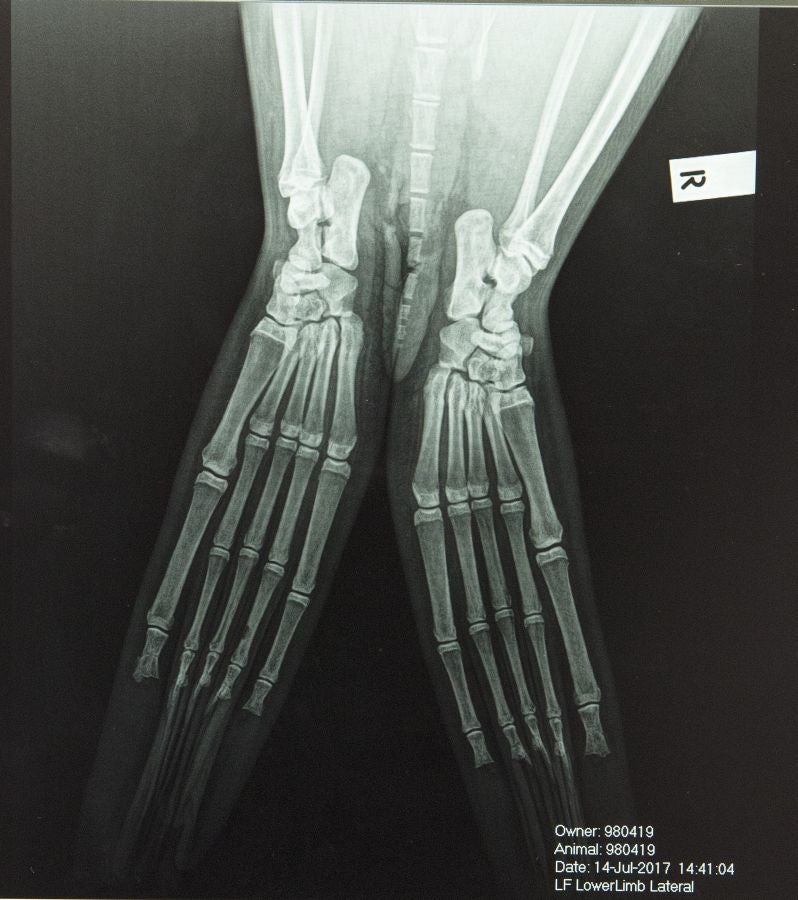

Un veterinario monitoriza la artritis de Tarwin, una foca que se encuentra en el zoológico de Melbourne, Australia. La artritis puede aparecer en gran número de animales envejecidos por eso, el equipo veterinario en el zoológico de Melbourne tiene estrategias para mantener la calidad de vida de los ejemplares afectados.